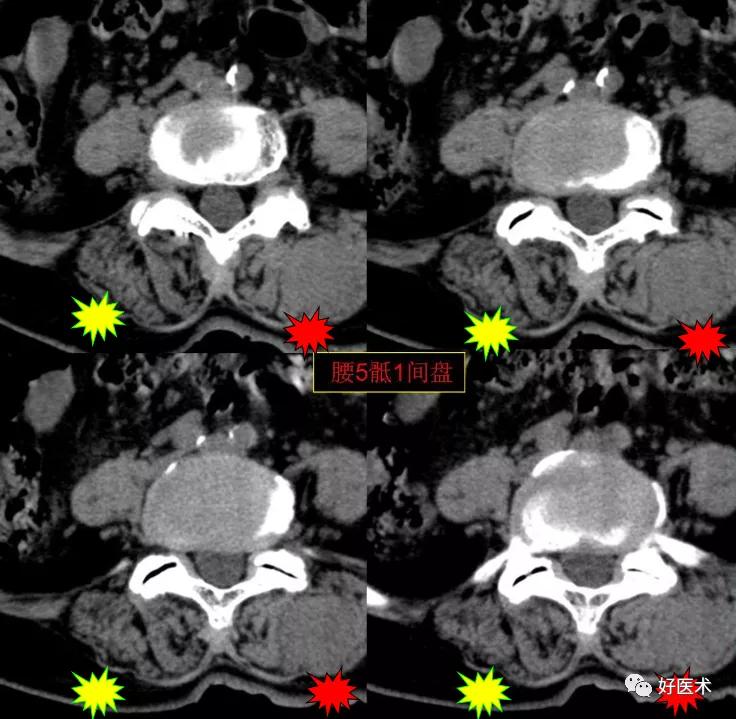

CT图像,腰椎常规采用序列扫描,腰椎体2层,腰间盘4层,层厚2.5mm,一般扫描范围包括腰2--骶1椎体及所属间盘。

腰5骶1间盘膨隆,双侧椎小关节积气

发现了什么?左侧竖脊肌较右侧明显肿胀饱满, 肌间脂肪间隙消失!!

终于知道了是什么鬼在作乱, 找到了左侧竖脊肌肿胀的元凶:肺癌转移。